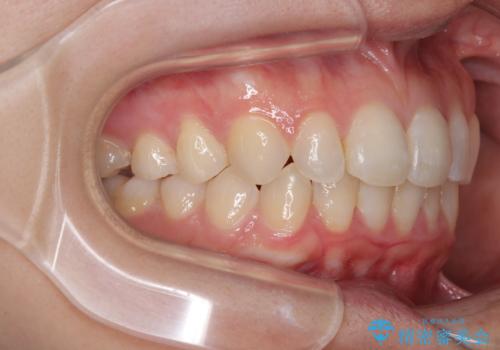

- 前歯のデコボコと歯肉に埋もれている奥歯を気にして来院された患者様です。

インビザラインでの治療を希望されていましたが、左右の下顎大臼歯が歯肉に埋もれており、特に右側は歯軸が顕著に傾斜していたため、インビザライン単独での治療は困難と判断し、ワイヤー装置を併用することとしました。

ワイヤー装置での下顎臼歯改善には時間がかかることが予想されたため、下顎のワイヤー矯正と並行して上顎をインビザラインで整え、その後インビザラインにより上下歯列を整える矯正治療を行うこととしました。

ワイヤー装置を併用したことで、レントゲン写真からも分かるとおり歯軸をしっかりと改善させることができました。